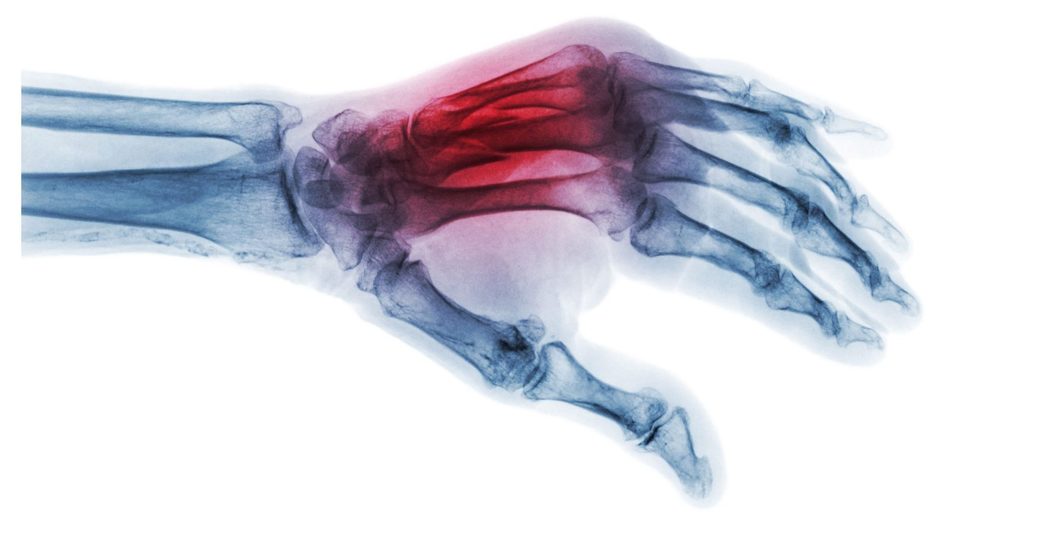

Substanţa, denumită „Bone-02”, promite să repare fragmentele de os în doar câteva minute, reducând necesitatea intervenţiilor chirurgicale invazive şi a implanturilor metalice.

Inspirat de modul în care stridiile aderă ferm la suprafeţe sub apă, echipa a încercat să reproducă acest mecanism pentru a fixa oasele fracturate. Potrivit dr. Xianfeng, adezivul reuşeşte o fixare precisă în două-trei minute, chiar şi într-un mediu bogat în sânge, condiţie întâlnită în timpul intervenţiilor chirurgicale.

Formula combină compuşi de calciu şi proteine specifice care asigură o legătură puternică, flexibilă şi sigură. Aplicarea sa necesită doar o incizie minimă, prin care adezivul este introdus direct în zona fracturată, sigilând fragmentele osoase în câteva minute.